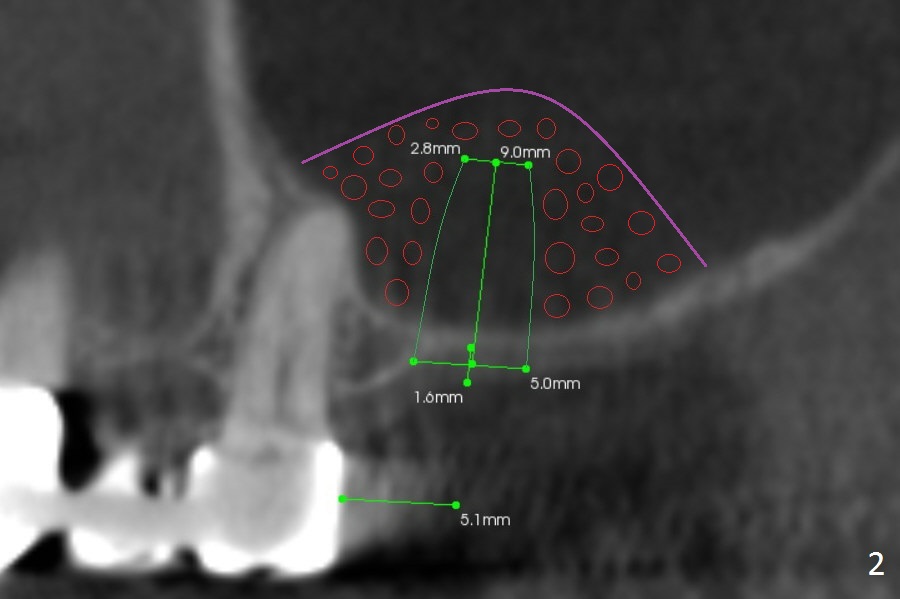

A 52-year-old woman is a dental phobic. Finally she agrees to have 1 implant placed in the upper left posterior region, where the sinus floor is paper thin (Fig.1). Use Magic Split for access for 2-3 mm deep, followed by Magic Lifter for 9 mm. If the latter does not engage, use Magic Drill in the Sinus Kit. Place PRF membranes (Fig.2,3 purple curved line) and allograft/Osteogen (circles) prior to 4 mm dummy implant. The 1st intraop PA will show whether the graft is sufficient or not. Since the mesial bone is thicker than the distal one (Fig.1,2), try to prevent the osteotomy from drifting distally (1).